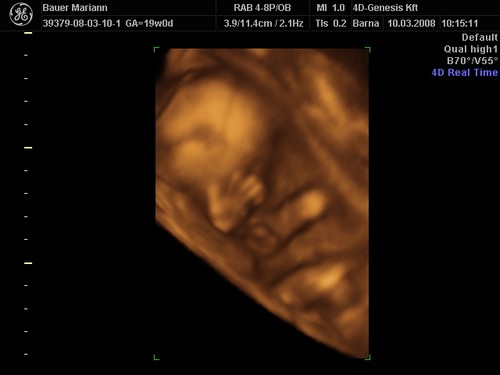

És egy tappancs 2008.03.08 19:45